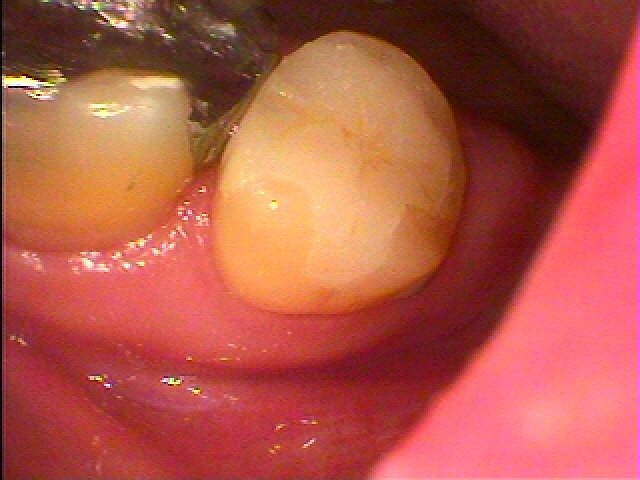

セレックセラミックにて修復しています

本来の歯のようにきれいに仕上がりました